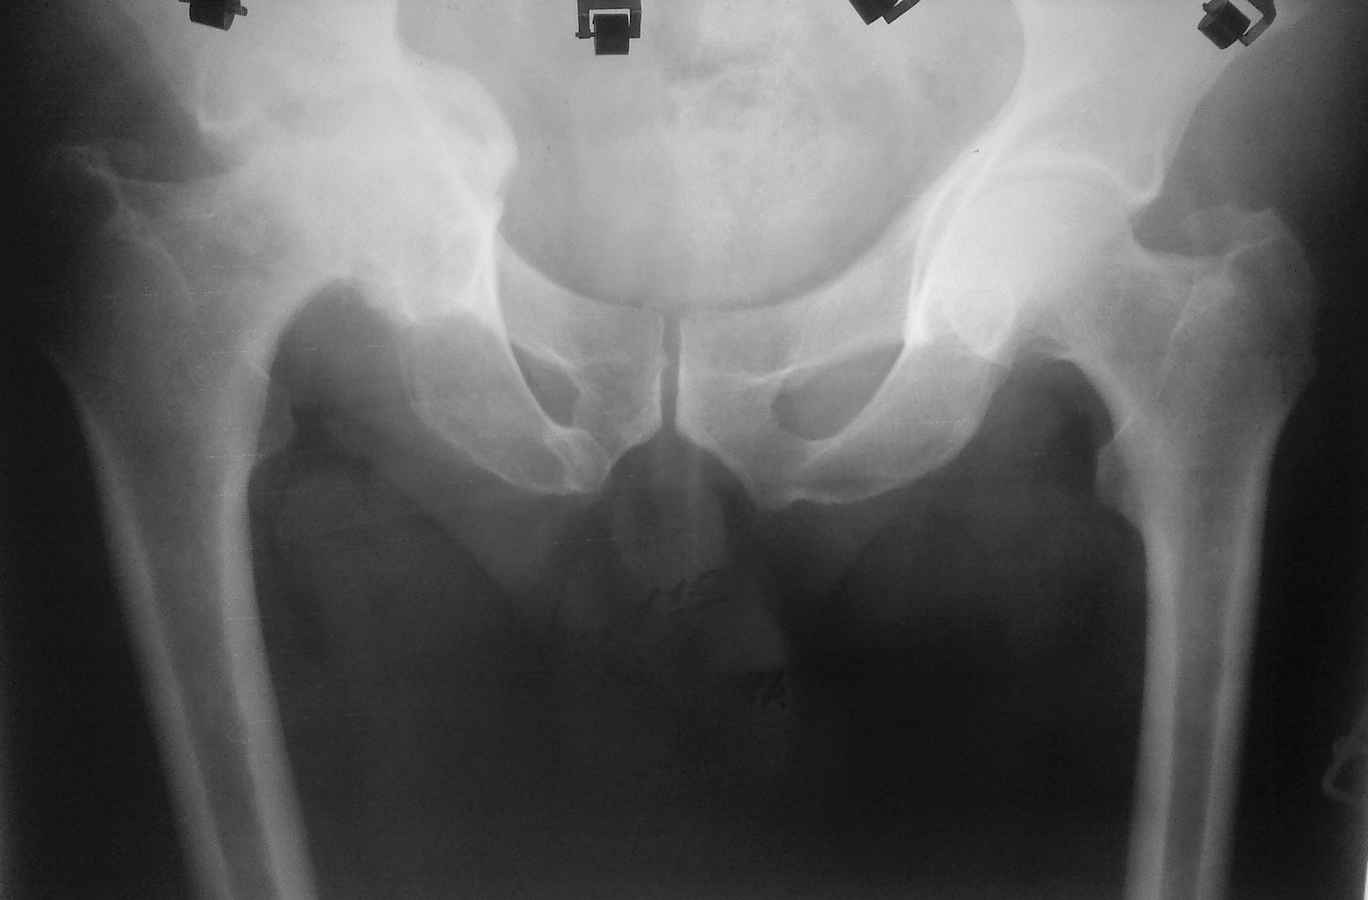

Здравствуйте. Уважаемые коллеги, поделитесь опытом у кого какая тактика при протрузионных коксартрозах

У нас в клинике принято выполнять костную пластику дна стружкой из гололки, а потом цементную чашку (снимки прилагаю). Выскажите свои взгляды на эту проблему, пожалуйста.

мы делаем пластику чипсами из головки, затем press fit.

А почему цемент. Лучше бесцементную чашу в данном случае. А Рыков Хабаровск

согласен, в цемент вряд ли прорастет даже аутокость. а вот в какой-нибудь Porocoat возможно.